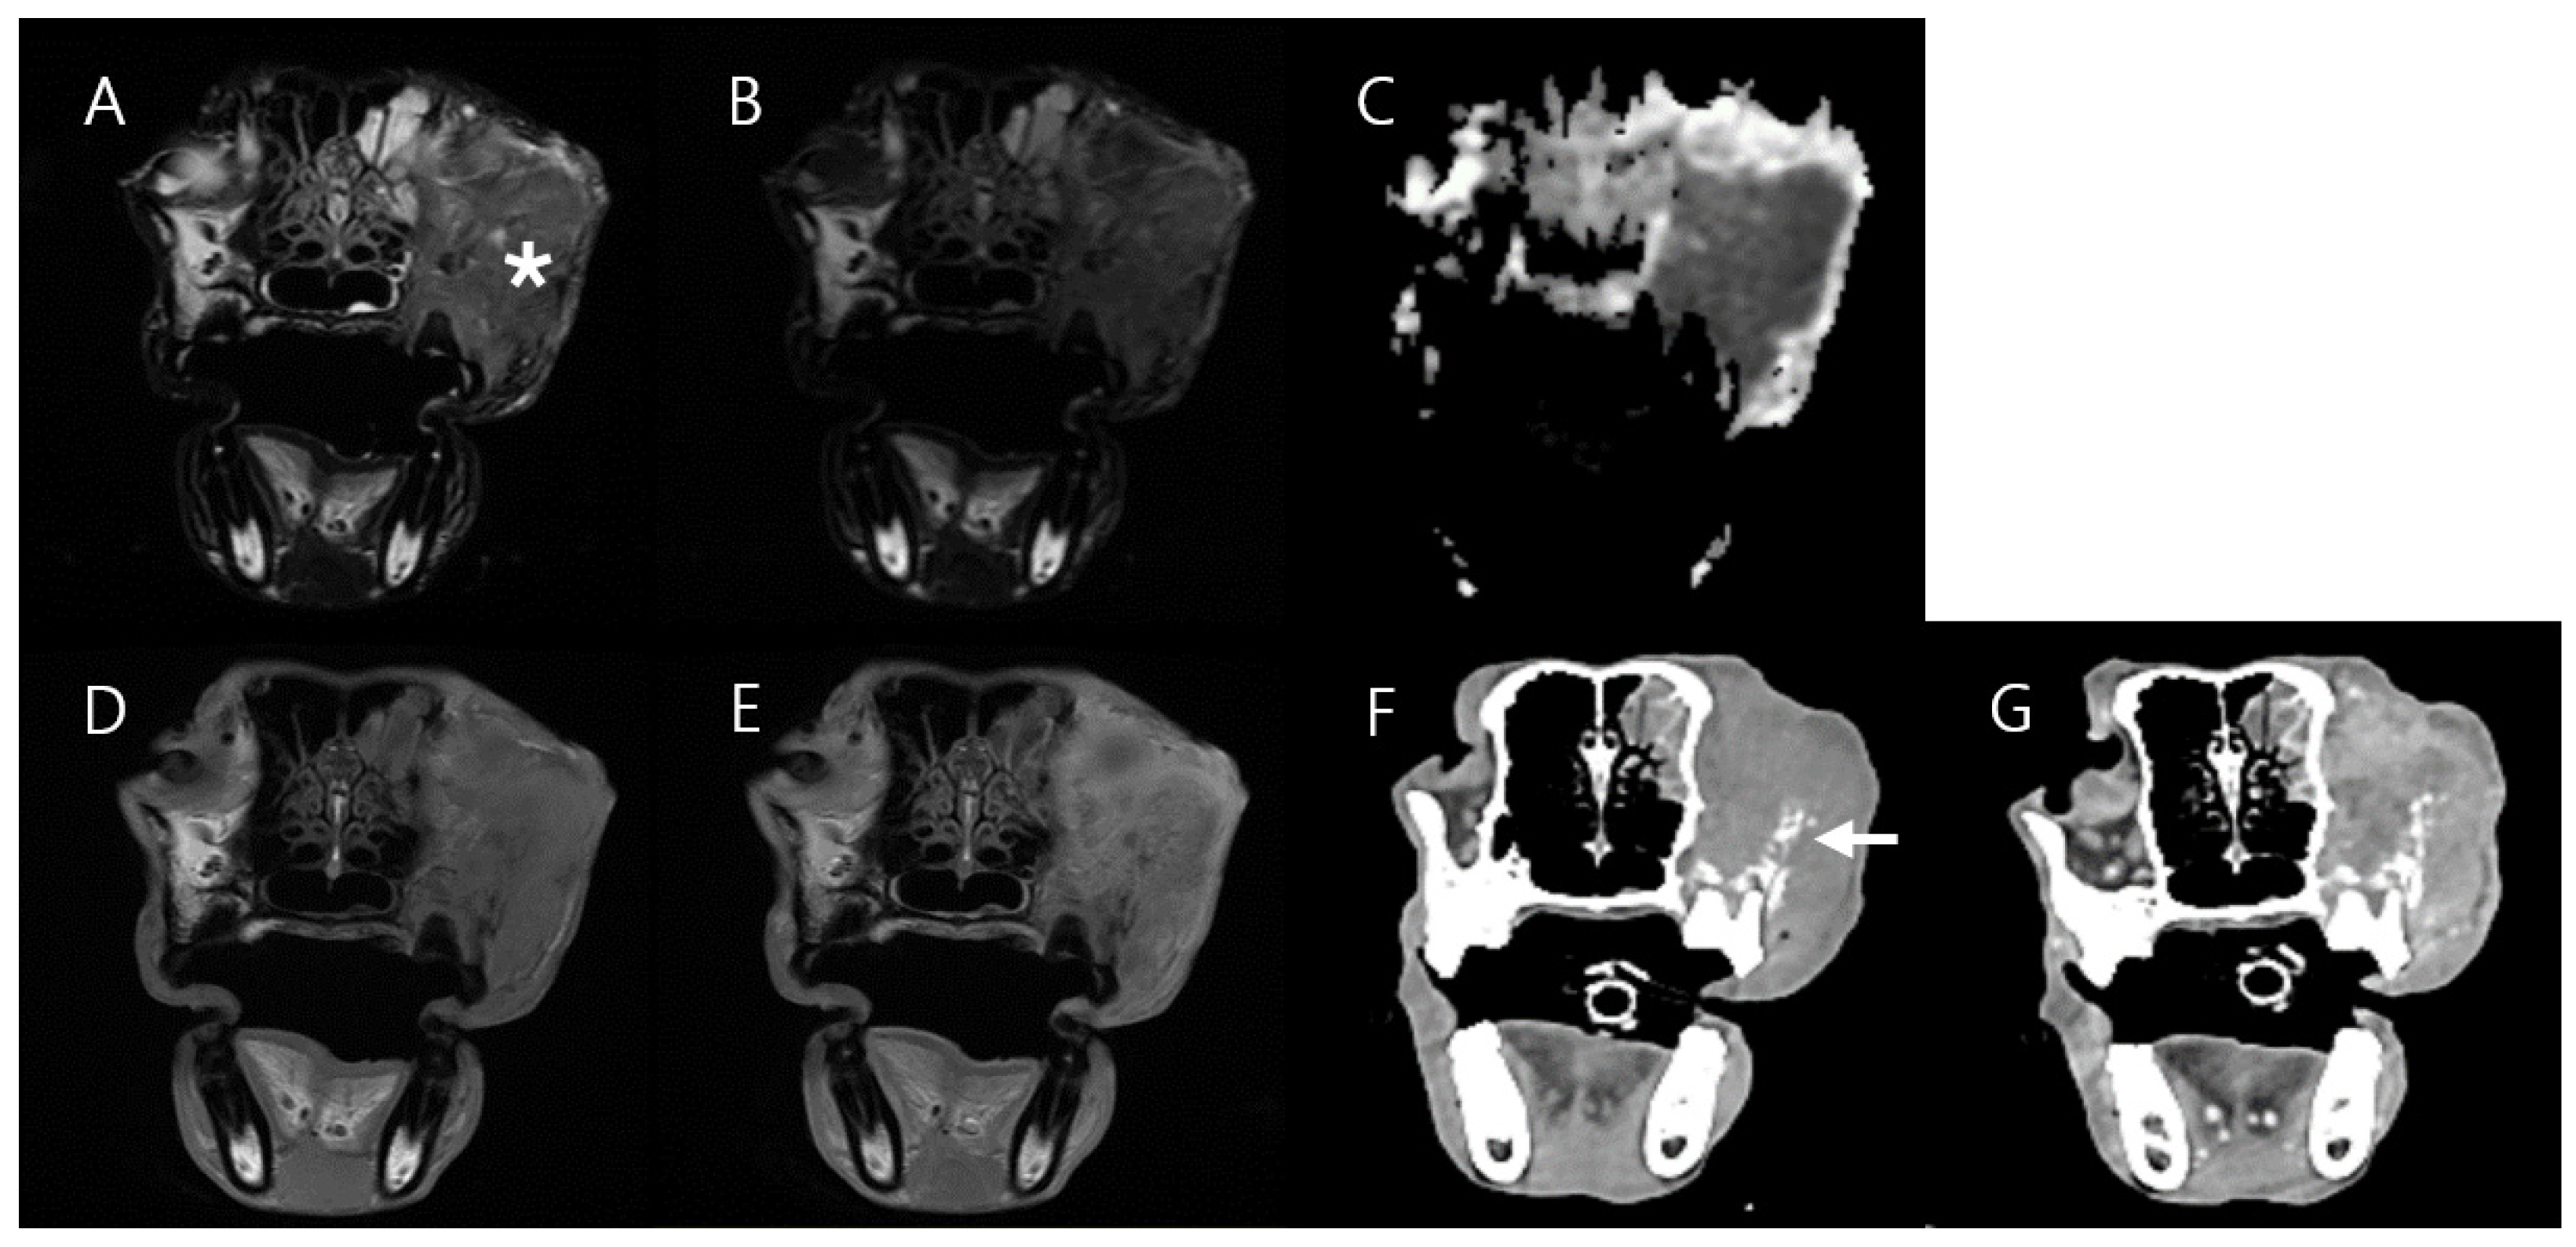

3.4. Case 4

| Case 3 * | Case 4 ** | |||

|---|---|---|---|---|

| Mass Type | Cholesteatoma | Normal Region (Contralateral Bulla) | Squamous Cell Carcinoma | Normal Region (Contralateral Muscle) |

| Ktrans (min−1), mean ± SD | 0.043 ± 0.1 | 0 | 0.24 ± 0.136 (Central mass region) 0.667 ± 0.143 (Peripheral mass region) | 0.058 ± 0.074 |

| kep (min−1) mean ± SD | 1.812 ± 2.318 | 0 | 0.83 ± 0.561 (Central mass region) 2.866 ± 0.568 (Peripheral mass region) | 0.57 ± 1.911 |

| Ve mean ± SD | 0.023 ± 0.052 | 0 | 0.296 ± 0.064 (Central mass region) 0.236 ± 0.038 (Peripheral mass region) | 0.144 ± 0.041 |

| Vp mean ± SD | 0.001 ± 0.014 | 0 | 0.103 ± 0.046 (Central mass region) 0.188 ± 0.048 (Peripheral mass region) | 0.065 ± 0.055 |

| TIC Type | Plateau | Absent | Progressive (Central mass region) Rapid wash-in, Slow wash-out (Peripheral mass region) | Progressive |